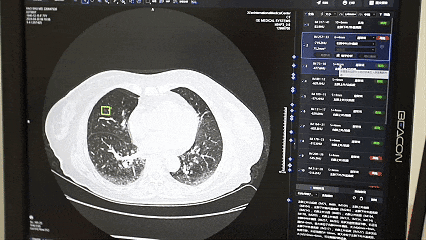

“智慧赋能”拉开该院系列微改革的帷幕。像上述王先生所体验的“诊间支付”,已在全院近百个诊室推开。这只是“便民就医少跑腿”多项举措中的一项。线上问诊、移动支付、智慧病房、数字化手术室、远程监测、智能随访以及AI诊断、秒等取药、智能导医、气动物流、机器人等,为医院插上智慧的翅膀,让智慧化遍布就医每一个环节,也让患者感受到数字技术带来的变化及智慧医院带来的快捷。

2025年2月20日,在西北首家本地化成功部署DeepSeek-R1大模型之后,该院又推出了“国医小助”智能辅助诊疗系统,在患者服务、辅助医疗诊断和医院管理三方面展现出强大的能力。院内智能导航精准引路、床旁移动结算、线上病案复印等服务陆续上线,让“信息多跑路,群众少跑腿”变为现实。